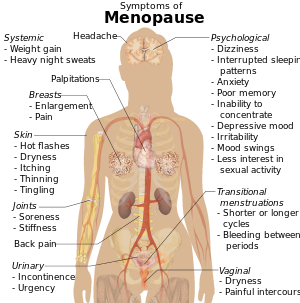

وقد تسبب مستويات الإستروجين المتناقصة، بعض الأعراض مع اقتراب المرأة من سن اليأس. على سبيل المثال، قد تقاسي العديد من النساء من حالات مفاجئة من الحرارة الشديدة والتعرق، تعرف باسم التوهجات الساخنة والتعرق الليلي. وقد تسبب هذه النوبات الشعور بعدم الراحة أو تؤدي إلى انقطاع النوم. كما قد يؤدي انخفاض الإستروجين أيضًا إلى جفاف وتهيج المهبل.

أعراض انقطاع الطمث